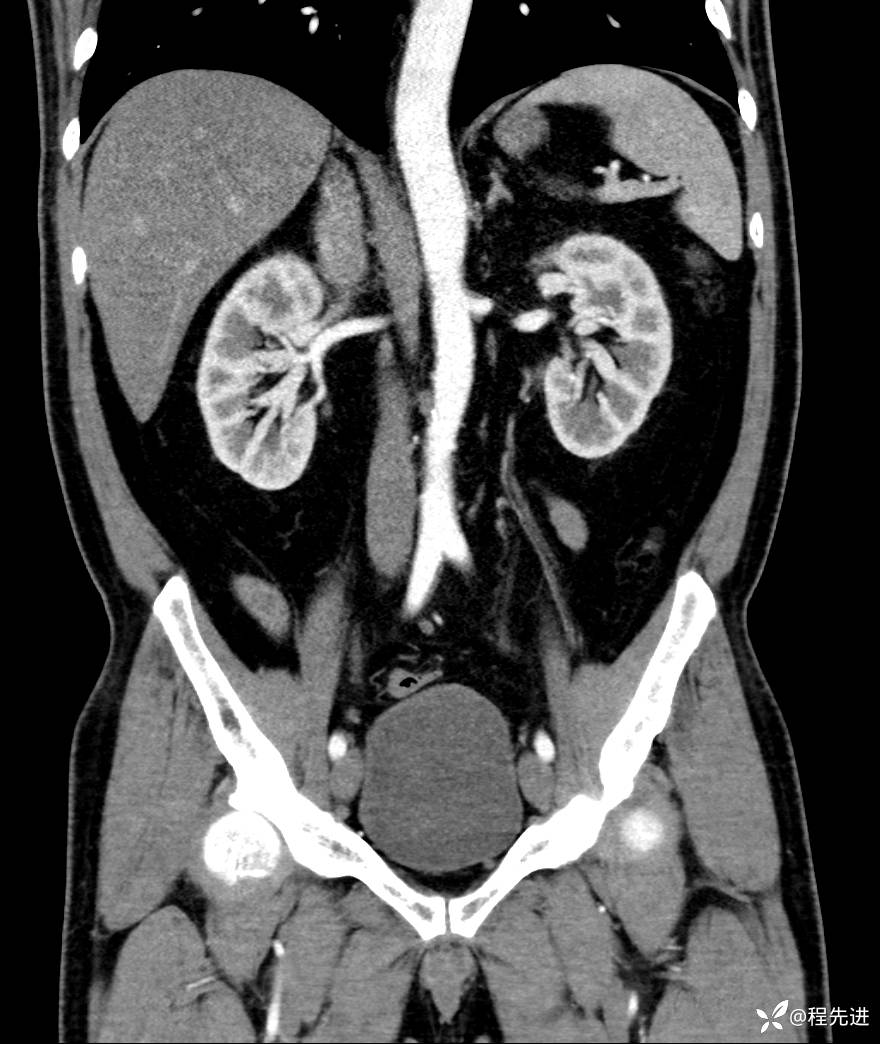

【腹盆】特别精彩病例|发现腹膜后肿物1月余

患者性别:男

患者年龄:42岁

主诉:发现腹膜后肿物1月余

现病史:患者1月余前查体,行超声检查提示:后腹膜囊实性肿块;慢性胆囊炎伴胆囊内结石;无腹痛腹胀,不伴腹泻发热等;偶感腰背部酸痛。

CT平扫+增强: